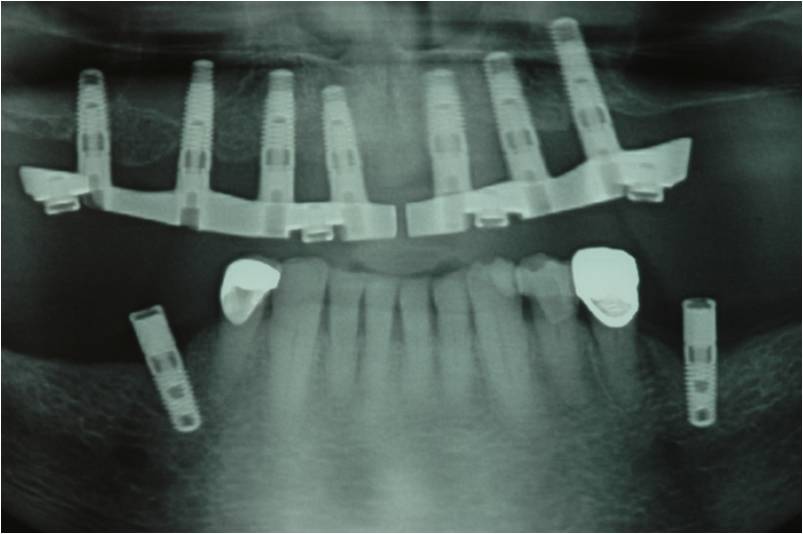

עקב חוסר בעצם ואי רצון מצד המטופל לעבור הרמות סינוס בוצע תיכנון ממוחשב של מיקום השתלים עוד בטרם ההשתלה.

ההשתלות בוצעו דרך שבלונה שהוכנה במדפסת תלת מימד בהתאם לקובץ הממוחשב.

סוג השיקום הוא " קבוע נשלף" FIXED DETACHABLE.

זהו שיקום המתפקד כמו גשר קבוע יציב לחלוטין אך ניתן להסרה וניקוי בצורה יעילה כפי ששום שיקום אחר אינו מאפשר.

זהו השיקום בה' הידיעה המומלץ לבני הגיל השלישי.